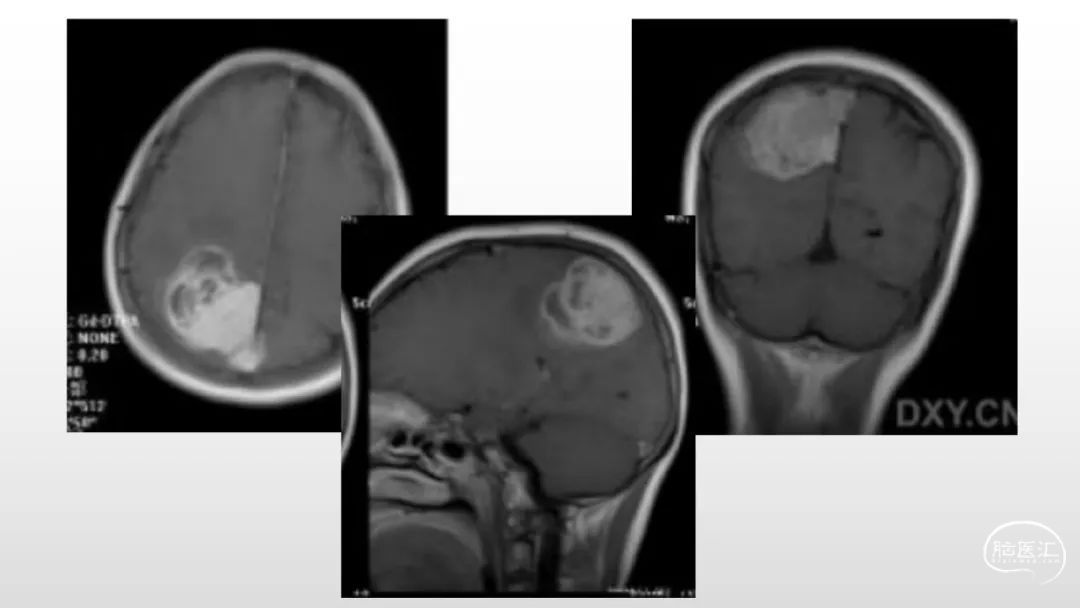

颅脑影像诊断基础知识讲座:脑膜病变